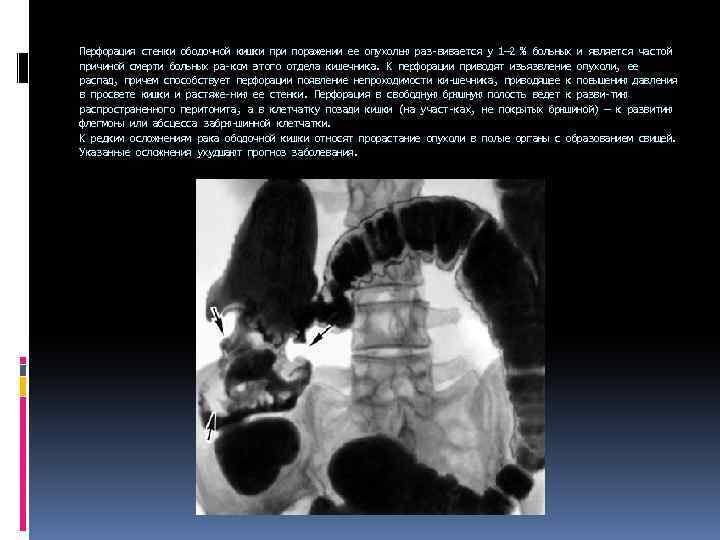

Перфорация стенки ободочной кишки при поражении ее опухолью раз вивается у 1— 2 % больных и является частой причиной смерти больных ра ком этого отдела кишечника. К перфорации приводят изъязвление опухоли, ее распад, причем способствует перфорации появление непроходимости ки шечника, приводящее к повышению давления в просвете кишки и растяже нию ее стенки. Перфорация в свободную брюшную полость ведет к разви тию распространенного перитонита, а в клетчатку позади кишки (на участ ках, не покрытых брюшиной) — к развитию флегмоны или абсцесса забрю шинной клетчатки. К редким осложнениям рака ободочной кишки относят прорастание опухоли в полые органы с образованием свищей. Указанные осложнения ухудшают прогноз заболевания.